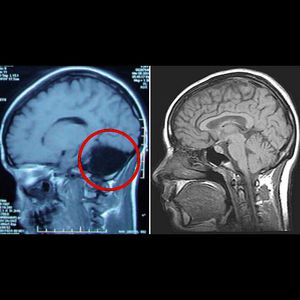

Complete cerebellar agenesis!! No brainer - notice a hole at the back where the cerebellum should be, compared to a normal brain! This woman has reached the age of 24 without anyone realising she was missing a large part of her brain. She is one of 9 people who are known to have lived without their entire cerebellum! The discovery was made when the woman was admitted to hospital complaining of dizziness and nausea. She told doctors she’d had problems walking steadily for most of her life, and her mother reported that she hadn’t walked until she was 7 and that her speech only became intelligible at the age of 6. Doctors did a CAT and MRI scans and immediately identified the source of the problem – her entire cerebellum was missing (see above). The space where it should be was empty of tissue. Instead it was filled with cerebrospinal fluid, which cushions the brain and provides defence against disease. The cerebellum, known as the “little brain”, is located underneath the two hemispheres. It looks different from the rest of the brain because it consists of much smaller and more compact folds of tissue, representing 10% of the brain’s total volume but contains 50% of its neurons. The cerebellum’s main job is to control voluntary movements and balance, and it is also thought to be involved in our ability to learn specific motor actions and speak. Problems in the cerebellum can lead to severe mental impairment, movement disorders, epilepsy or a potentially fatal build-up of fluid in the brain. However, in this woman, the missing cerebellum resulted in only mild to moderate motor deficiency, and mild speech problems such as slightly slurred pronunciation. Source - New Scientist Journal.